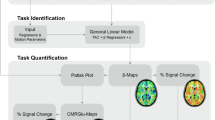

After background correction, all resulting scans had seven frames. Spatial processing and statistical analysis were done with SPM (http://www.fil.ion.ucl.ac.uk/spm/). The frames within each scan were realigned, and the first 10-s frame was discarded from analysis because of low counts and relatively high variability. The remaining six frames were then summed in all possible permutations of consecutive frames (see also Fig. 6.1). The summed images were spatially normalized (affine only) to the SPM [15O]-H2O template and smoothed with a 10-mm kernel.

The same contrast analysis, motor task versus control task, resulted in markedly different activation patterns depending on the time interval that was analyzed (indicated by white bars). Small arrows in the glass brains indicate the voxel with the highest t-value. All results are thresholded at p uncorrected < 0.001

2.4 Statistical Analysis

Data from all experimental tasks were modeled with a general linear model, with a proportional scaling step. Volunteers and experimental tasks were modeled as factors (multi-subject: conditions and covariates). Contrast images between motor task and control task were calculated for all the different time intervals. Statistical threshold was set to p < .001, uncorrected for multiple comparisons. Glass brains with activated voxels as a function of the selected time interval are presented in Fig. 6.1. The size of reported and displayed clusters is at least eight voxels.

We used the number of activated voxels in the activated clusters and its Z value as a primary outcome (Fig. 6.2).

The same contrast analysis, motor task versus control task, resulted in different results, depending on the time interval that was analyzed. Two clusters (first column) had different sizes (middle column) and different statistical significance (last column) depending on the period. The largest activation in sensorimotor cortex was found for the period 10–40 s while for cerebellar it was obtained for 20–120 s. The statistical power for both clusters was maximal for the period 20–50 s

Figure 6.1 shows the intervals that were compared (in white) along with the brain activation patterns (t-distribution maps in a lateral glass brain) that resulted from all of these comparisons.

Two robust brain activation loci were present for in the majority of compared intervals: the dorsal sensorimotor cortex and the medial part of the anterior cerebellum. As can be seen in the top rows of this figure, significant rCBF differences were also found with the shortest duration of the time period: 10 s. The 10 s interval that resulted in the largest activation was 30–40 s after injection of the radiotracer. The period compared clearly had a strong influence on the activation maps: both activation clusters were highly variable and the sensorimotor cluster was sometimes completely absent (for periods 50–60 and 50–120 s).

The sizes of the two clusters were very dependent on the time interval compared, and, moreover, the period resulting in maximum cluster size was very different for the two clusters. Figure 6.2 gives a matrix representation of the interval dependency of cluster size (middle column) and cluster significance (far right column).